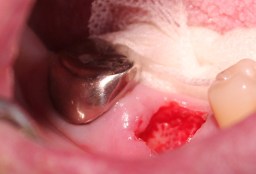

創面をラバーダムで覆い、テック(仮歯)を

装着